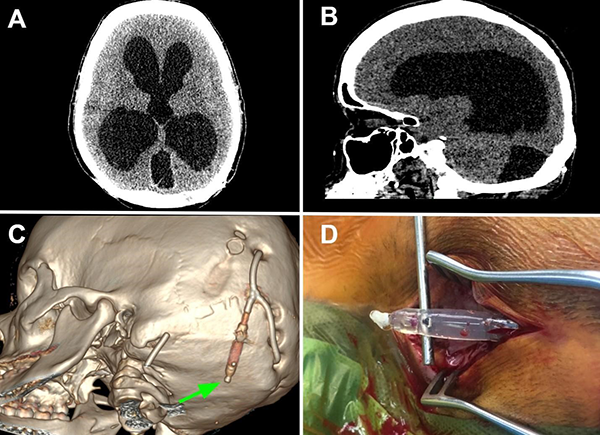

Tras 2 meses, la paciente volvió a consultar en guardia por náuseas, cefalea bifrontal con irradiación holocraneana de intensidad moderada y vómitos. Al examen físico se constató limitación de la mirada superior y colección líquida sobre herida craneal de derivación. Se realizó TC de cerebro con evidencia de ventriculomegalia y desconexión de catéter distal a la válvula (Figura 1). El estudio radiográfico reveló migración caudal del segmento distal del catéter al corazón (Figura 2). El segmento migrado fue rescatado mediante un abordaje endovascular transfemoral, en el cual se enroscó el catéter migrado con un catéter pigtail y se lo desplazó hasta la vena ilíaca primitiva izquierda para luego ser capturado a nivel ilíaco con un lazo trilobulado (Figura 3).

Figura 1. A y B. Corte axial y sagital de TC de cerebro evidenciando marcada hidrocefalia supratentorial. C. Reconstrucción 3D de dicha tomografía, se observa desconexión del catéter distal (flecha verde). Aclaración: sobre mastoides izquierda se evidencia catéter calcificado de válvula previa abandonada. D. Imagen intraquirúrgica con evidencia de desconexión de segmento distal.